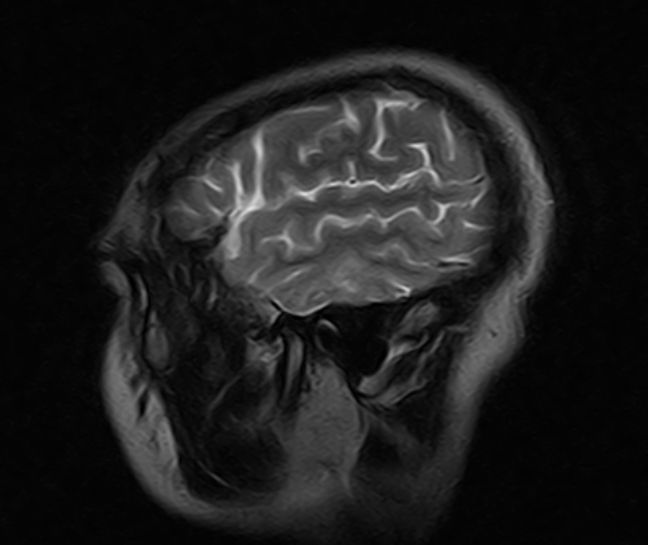

标题: MRI2379:30岁,男,癫痫10年,请各位看一下;CT示:左颞叶钙 [打印本页]

标题: MRI2379:30岁,男,癫痫10年,请各位看一下;CT示:左颞叶钙

左颞叶区见不规则点状混杂信号影

考虑血管畸形

支持2楼 左颞叶区见不规则点状混杂信号影,考虑动静脉畸形。

考虑左侧颞叶脑血管畸形(avm)。

考虑左侧颞叶脑血管畸形(avm)。----t1低等高混杂信号,t2等高信号周边较多流空血管影[冠状位明显],mra左侧大脑中动脉受压,远侧聚集.